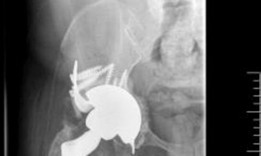

A highly porous metal cup is then impacted into the defect. The cup is often placed in an off-axis orientation, prioritizing host bone contact and initial stability over anatomic version and inclination. The subsequent cementation of the liner into the cage will correct the final articular geometry. If large cavitary defects remain behind the cup, highly porous metal augments or impacted cancellous allograft are utilized to fill the voids and support the primary shell. Multiple multi-hole screws are placed through the cup into the superior dome and posterior column to maximize initial fixation.

Cage Contouring and Fixation

The appropriate cage is selected based on preoperative templating and intraoperative trialing. The inferior flange is contoured to fit into the prepared ischial slot. The superior flange is contoured to lie flush against the lateral aspect of the ilium. Proper contouring is critical; a poorly contoured cage will experience high bending moments and subsequent fatigue failure.

The cage is inserted by first seating the inferior flange into the ischium. The superior flange is then impacted against the ilium. The cage should sit intimately against the previously placed highly porous cup. Fixation begins with the placement of cortical or cancellous screws through the superior flange into the dense bone of the ilium, aiming toward the sacroiliac joint. Screws are also placed through the central dome of the cage, passing through the cage, the underlying porous cup, and into the host bone, effectively locking the two components together. Care must be taken to avoid the superior gluteal neurovascular bundle during superior flange screw placement and the external iliac vessels during anterior screw placement.

Liner Cementation and Final Reduction

Once the cage is rigidly fixed, the surgical site is thoroughly irrigated and dried. A highly cross-linked polyethylene liner is selected. The back of the liner is often scored to enhance cement interdigitation. High-viscosity polymethylmethacrylate bone cement is applied to the inner surface of the cage.

The liner is pressurized into the cement mantle. The critical advantage of this technique is that the surgeon can manipulate the version and inclination of the polyethylene liner independently of the orientation of the underlying cage and cup. The liner is held in optimal anatomic orientation (typically 15 to 20 degrees of anteversion and 40 to 45 degrees of inclination) until the cement fully cures. Excess cement is meticulously removed to prevent third-body wear. The femoral component is then reconstructed as dictated by the femoral defect, and the hip is reduced and assessed for stability through a full range of motion.